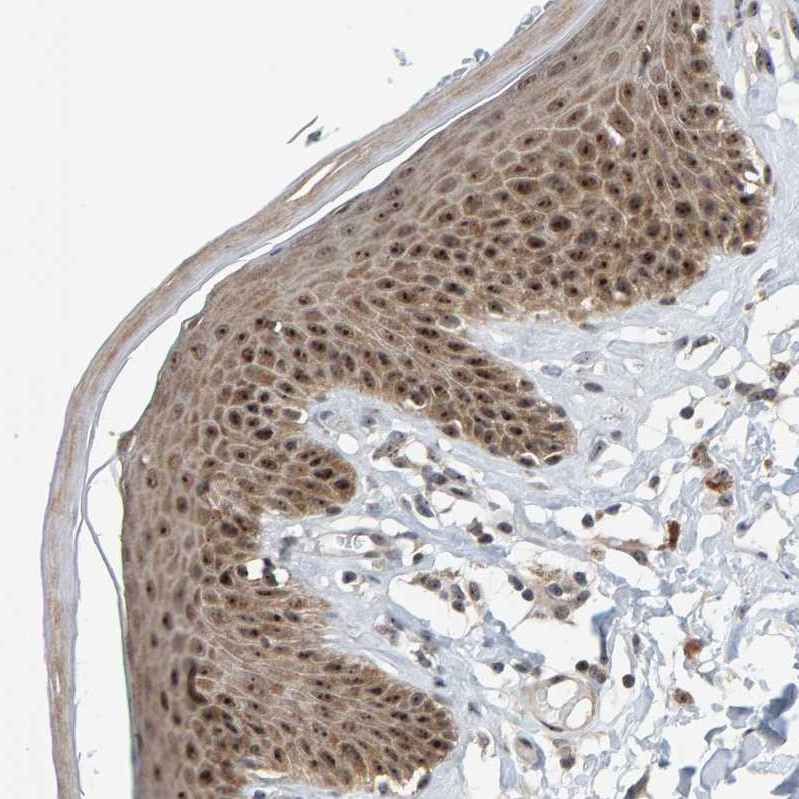

Immunohistochemical staining of human ovary shows strong nucleoli positivity in follicle cells.